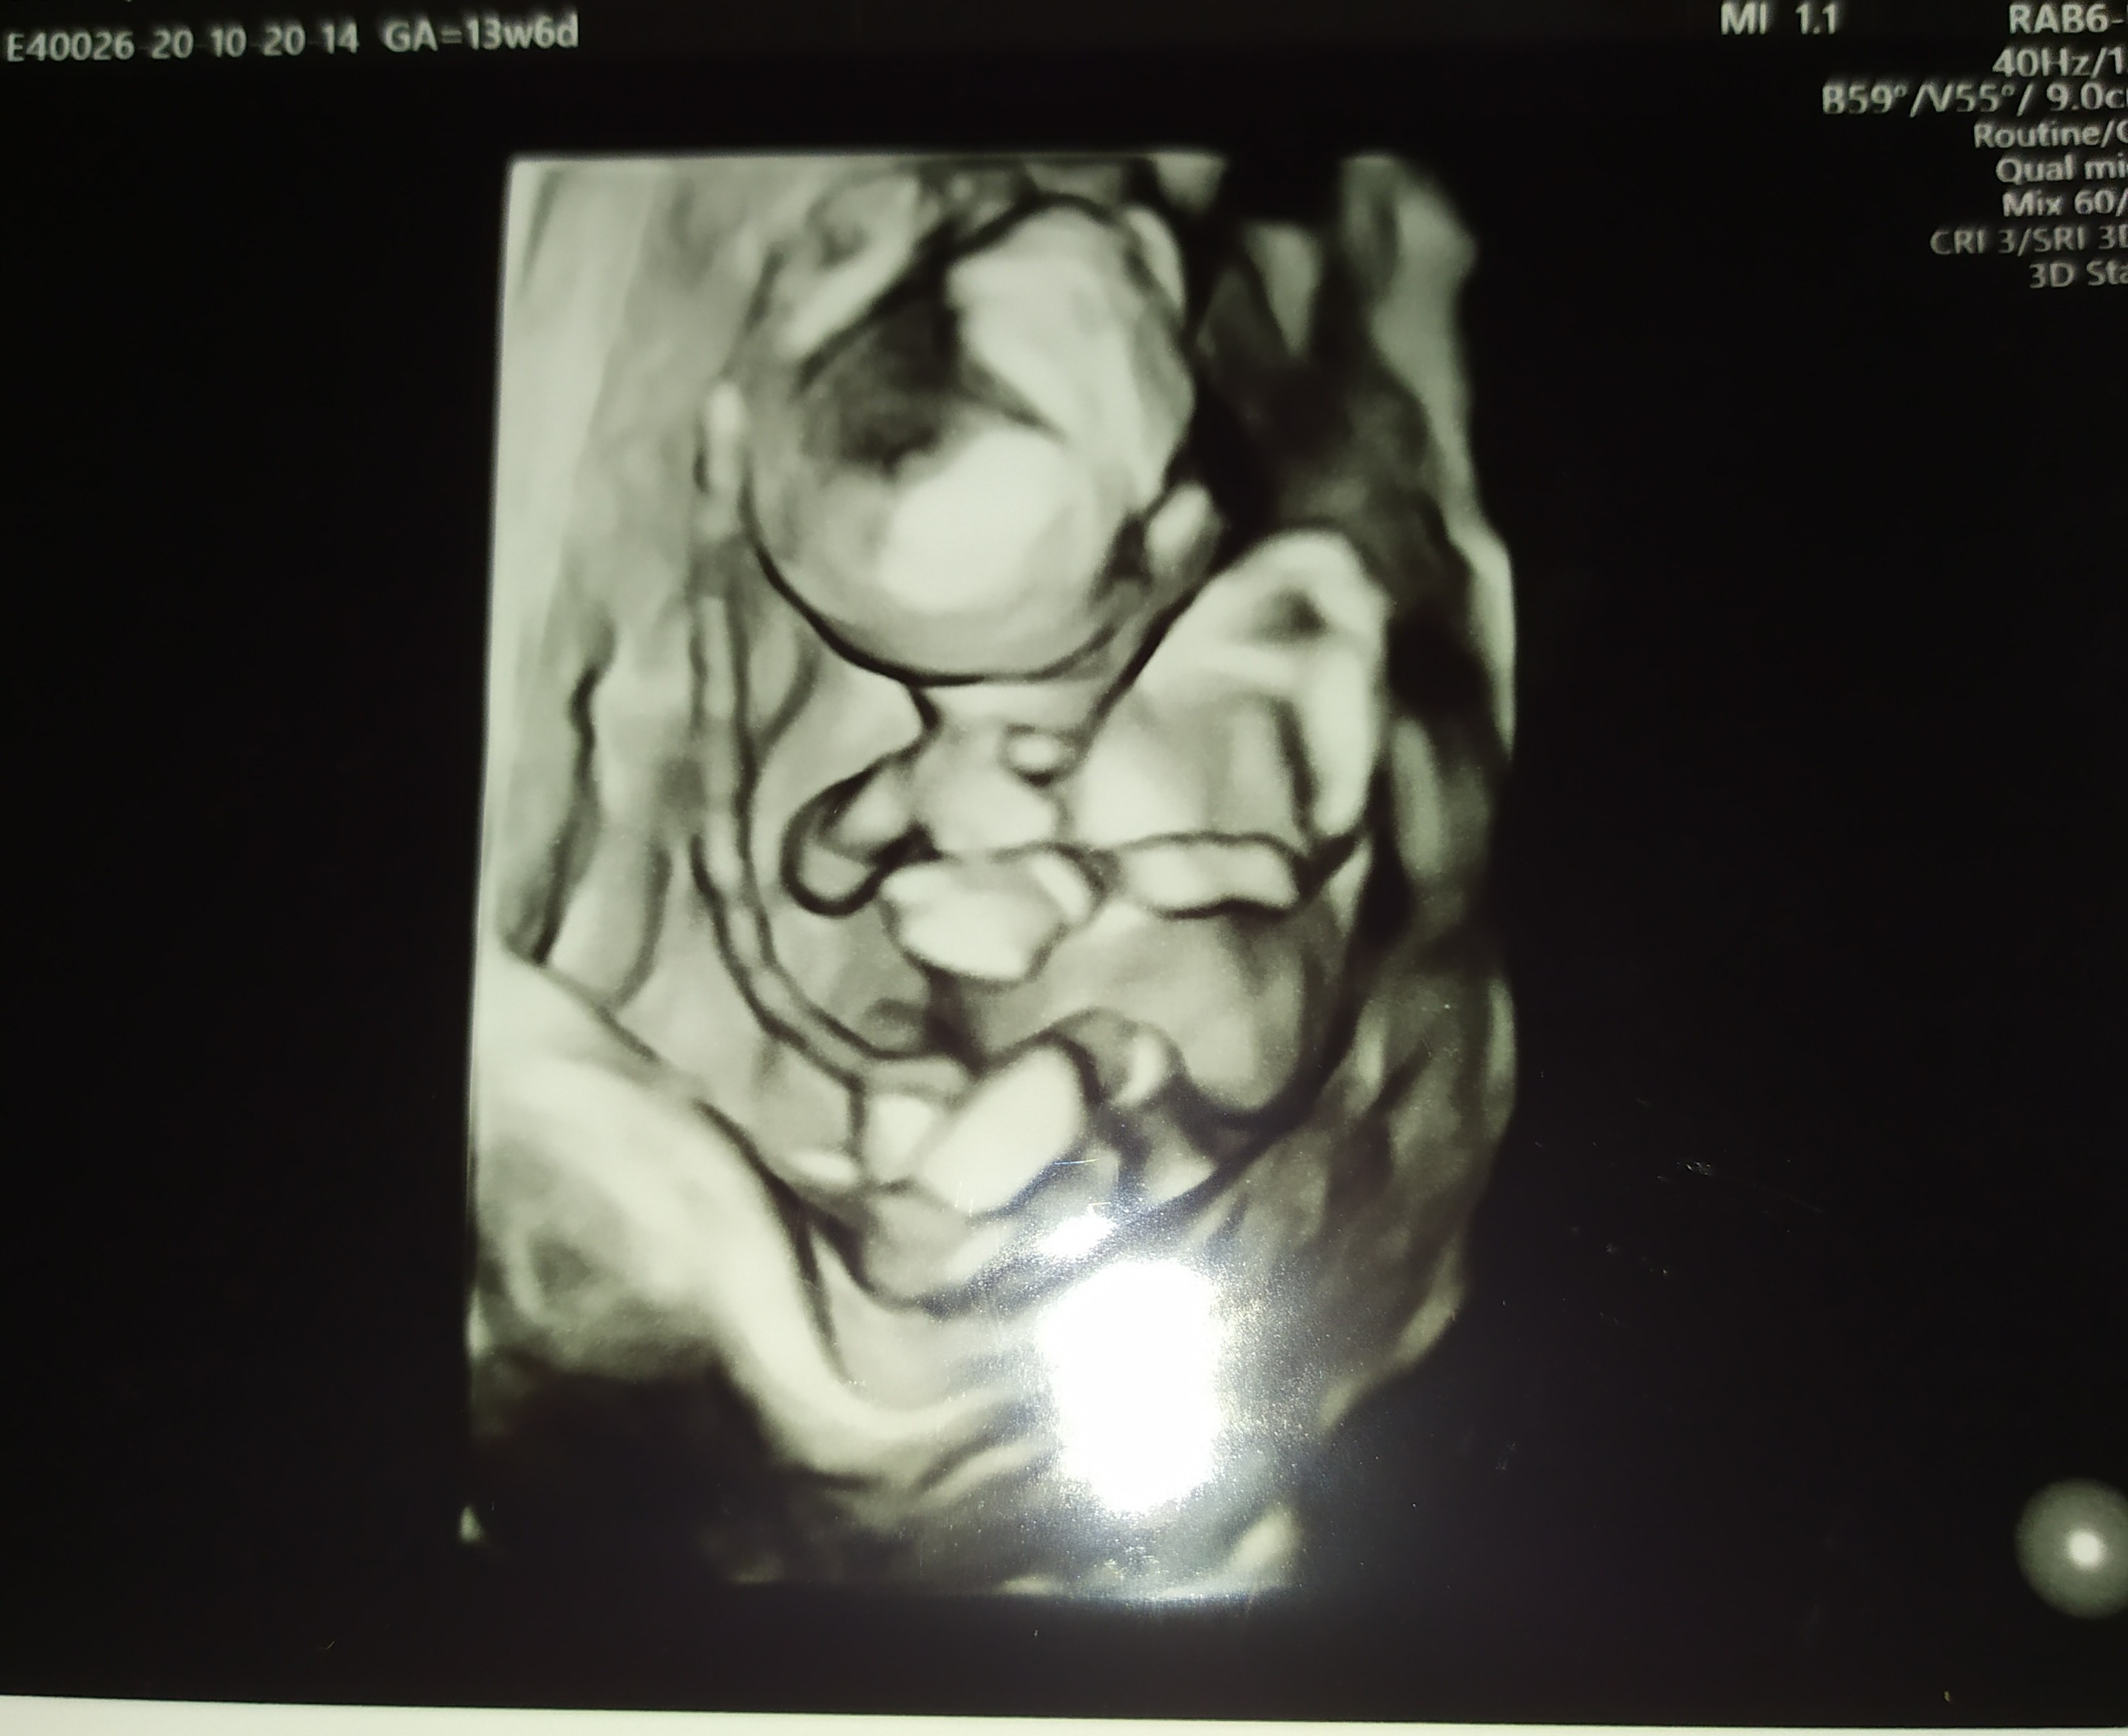

My po USG. Dzidzia książkowo rośnie, oczywiście wypinala dupsko, żebym tylko nie popatrzyła co ma w kroku 🙈😂

Wg wielkości dziecka niby 15tc, ale ogólne USG pokazuje na 14+5. Waży 105g🤔🤔🤔🤔 czy to jakoś nie za dużo? Czytałam ile na ten czas powinno mieć dziecko i piszą, że mniej. No, Ale lekarz powiedział, że rozwija się książkowo i Mu wierzę. A co mnie najbardziej ucieszyło , to to że miesniak zmalal 🥰 z 8cm do 7cm 😁

Witajcie, dzisiaj już trochę lepiej, leżę po śniadaniu żeby zostało ;) A zaraz do pracy. Odnośnie wczorajszego USG to lekarz był bardzo miły ( @Kamiśka :) nastawiałam się, że może być średnio ale chyba faktycznie miał wtedy gorszy dzień), wszystko pokazywał i objaśniał, nawet liczyliśmy palce u rączki [emoji2] Widziałam żołądek i pęcherz moczowy, serducho biło 152/min. Przezierność 1,8, ryzyko z wieku po USG spadło czterokrotnie :)Zobacz załącznik 1190837Zobacz załącznik 1190838Zobacz załącznik 1190839